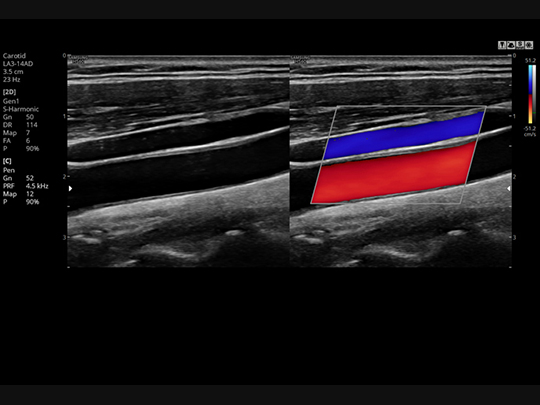

S-Flow™

A sophisticated color Doppler technology with greater sensitivity, S-Flow can detect low-intensity blood flow. It enables accurate diagnosis when blood flow examination is especially difficult.

S-Harmonic™

This new harmonic technology provides greater image uniformity from near to far field while reducing signal noise.

Samsung HS60 Compatible Transducers / Probes

Linear array transducers

LA3-14AD

- Application: abdomen, musculoskeletal, small parts, vascular